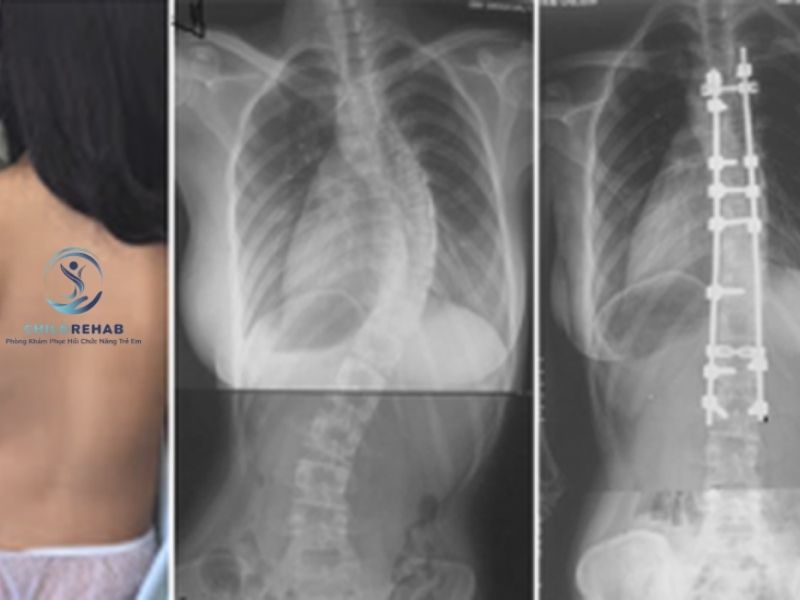

Trên thực tế, chụp X-quang là một phương pháp chẩn đoán quan trọng giúp đánh giá mức độ cong vẹo cột sống ở trẻ một cách chính xác. Tuy nhiên, không phải trường hợp nào cũng cần chụp ngay. Việc chỉ định chụp X-quang cần dựa trên đánh giá ban đầu từ chuyên gia, bao gồm việc quan sát các dấu hiệu cong vẹo cột sống ở trẻ, kiểm tra tư thế và xác định nguy cơ tiến triển. Nếu lạm dụng chụp X-quang khi chưa cần thiết, trẻ có thể bị phơi nhiễm tia X nhiều hơn mức cần thiết.

Ngược lại, nếu bỏ qua việc chẩn đoán hình ảnh trong những trường hợp cần thiết, phụ huynh có thể không nắm rõ mức độ cong vẹo, dẫn đến việc lựa chọn sai phương pháp can thiệp. Điều này ảnh hưởng trực tiếp đến hiệu quả điều trị, đặc biệt khi áp dụng các bài tập cho trẻ bị cong vẹo cột sống mà không hiểu rõ tình trạng cụ thể.

Cong vẹo cột sống ở trẻ có thể cần chụp X-quang để đánh giá chính xác, nhưng không phải lúc nào cũng cần thiết. Điều quan trọng là thực hiện đúng thời điểm và theo chỉ định chuyên môn.